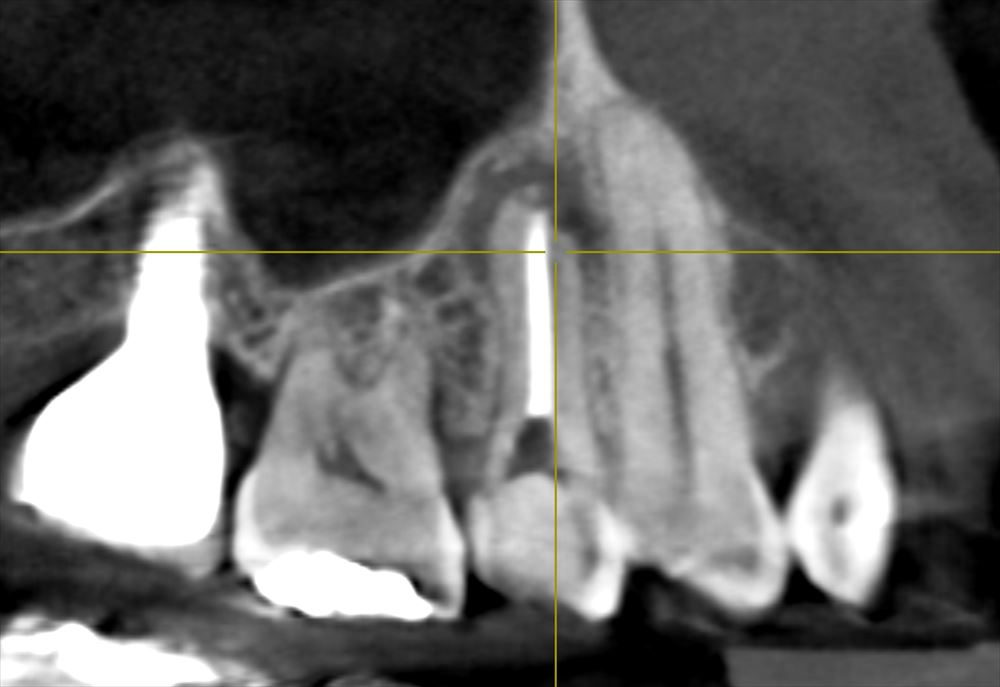

CTでも近遠心で確認

頬側の骨がないですね。この治療で再生してくるはずです。

ちなみに下記のCTに写っているインプラントは私がすべて行った物です。下もあわせて5本。すでに下は9年経過です。まったく問題ありません。